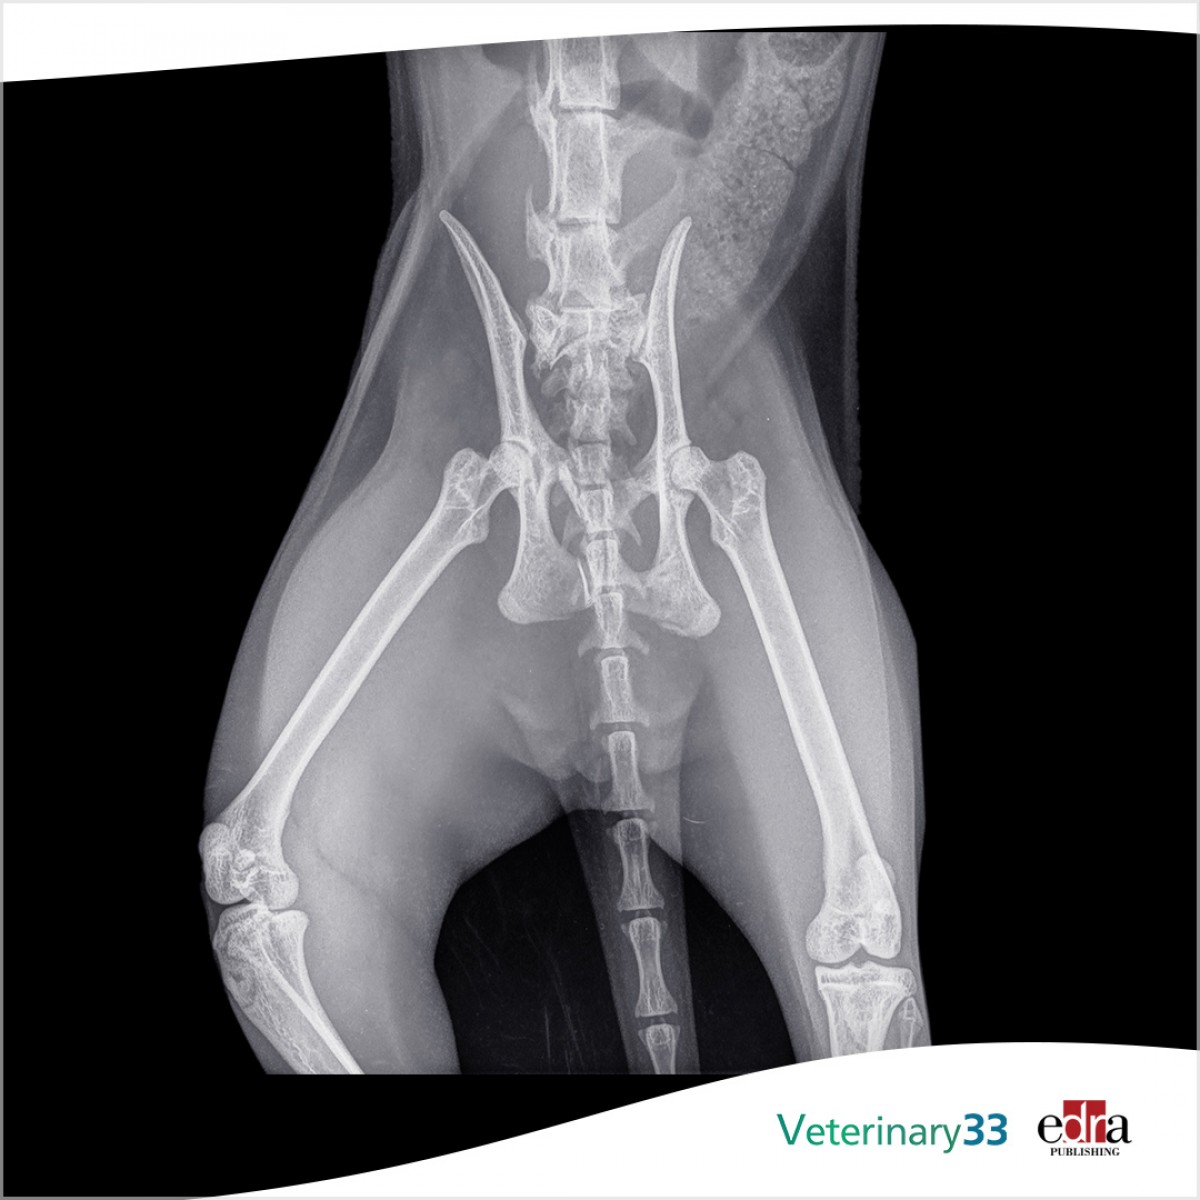

Sacral fracture stabilisation using dorsal transiliac locking plates: 12 cases (2017-2023)

Objectives: To describe the clinical presentations, outcomes and complications associated with the use of dorsal transiliac locking plates to stabilise sacral fractures in dogs and cats.

Results: Eleven dogs and one cat with a mean age of 3.1 years (range 0.6 to 8.8) were included. Eleven patients presented following a motor vehicle accident and most were either non-ambulatory (n=8) or displayed severe unilateral hindlimb lameness (n=4). Nine sacral fractures were considered Anderson type II and three Anderson type V. The plate fixation was augmented with additional surgical stabilisation in 11 cases. Eleven patients were ambulatory at discharge and all cases healed uneventfully without major surgical or postoperative complications. Long-term follow-up (>60 days) was available in 10 animals at a mean of 694 days (range 65 to 1805) and owner-assessed outcomes via questionnaire were reported as good to excellent in all cases.

Clinical significance: The application of transiliac locking plates provided sufficient stability to facilitate sacral fracture healing with minimal clinical complications. This method represents a robust and safe option to stabilise sacral fractures in dogs and cats, offering an alternative to iliosacral lag screw fixation.